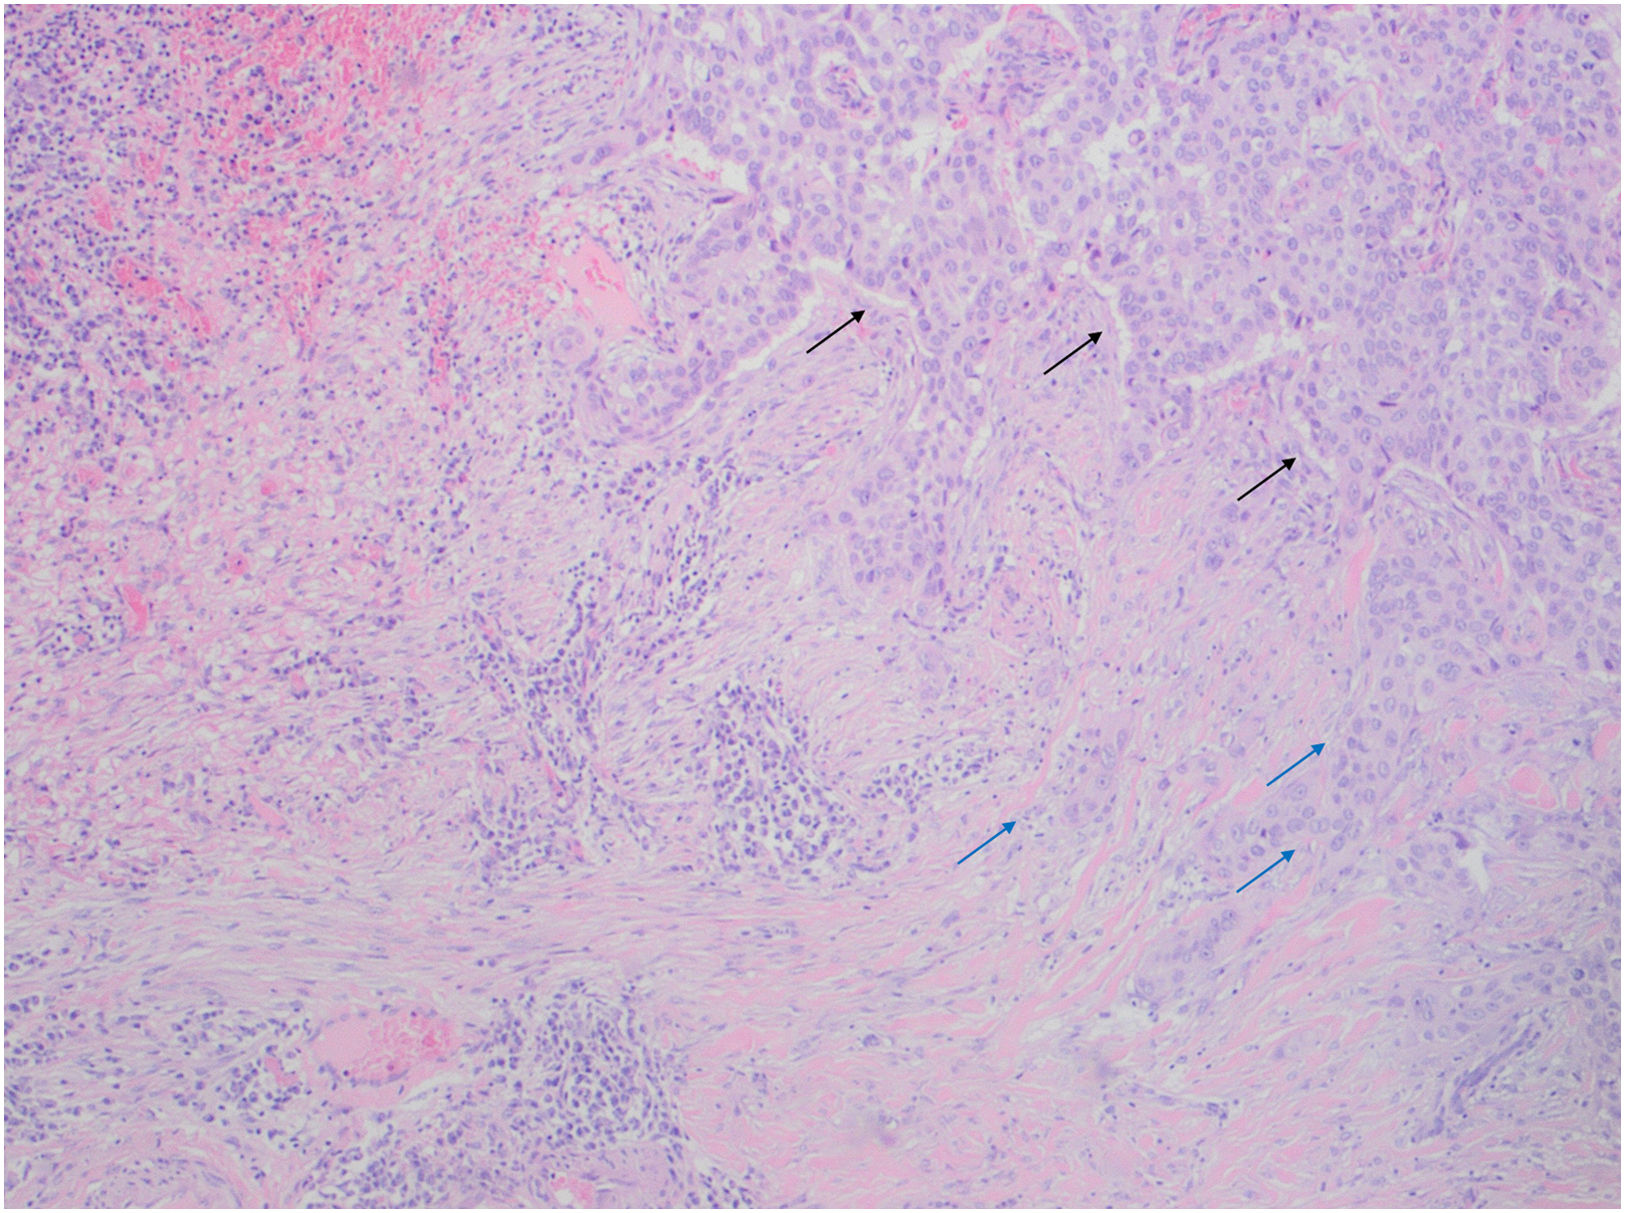

The patient was lost to follow-up and returned 2 years later with a lesion consisting of a 13×10-cm infiltrative plaque and a 4×4cm central ulcer (Fig. 1A). Surgical excision of the central ulcer was performed. Histology revealed areas consistent with BCC differentiation, positive for Ber-Ep4, together with areas of squamous differentiation with negative immunohistochemistry, leading to a diagnosis of BSC (Figs. 2 and 3).

Histopathology of the central ulcer. (A) Hematoxylin–eosin, 40×: squamous differentiation, predominant in central ulcer sections. (B) Hematoxylin–eosin, 40×: basaloid differentiation with peripheral palisading and clefting near the resection margins. (C) Ber-Ep4, 4×: strong positivity in BCC areas and negativity in regions of squamous differentiation. (D) Ber-Ep4, 4×: section from an ulcer margin showing Ber-Ep4–positive basaloid cells and Ber-Ep4-negative squamous cells.